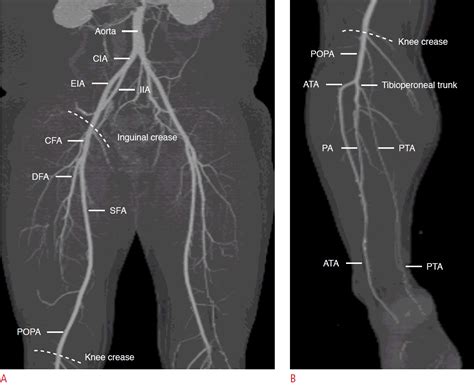

• The popliteal artery, which runs behind the knee and divides into the anterior tibial artery, posterior tibial artery, and peroneal artery.

• The anterior tibial artery, which supplies blood to the anterior compartment of the leg and continues down to the dorsum of the foot as the dorsalis pedis artery.

• The posterior tibial artery, which supplies blood to the posterior compartment of the leg and continues down to the sole of the foot, where it divides into the medial and lateral plantar arteries.

• The peroneal artery, which supplies blood to the lateral compartment of the leg and anastomoses with the anterior and posterior tibial arteries.

These arteries branch further into smaller vessels, ensuring that every part of the lower limb receives an adequate blood supply.